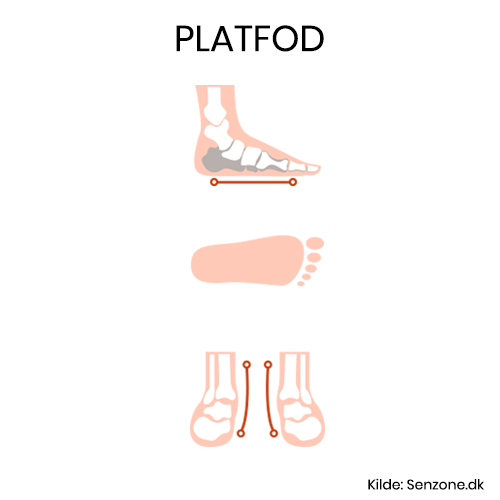

Platfod indlæg - Hvad er platfod? - Alt hvad skal vide!

Platfod indlæg - Hvad er platfod? - Alt hvad skal vide!

ID: YfFBQ8SJuI

From: senzone.dk